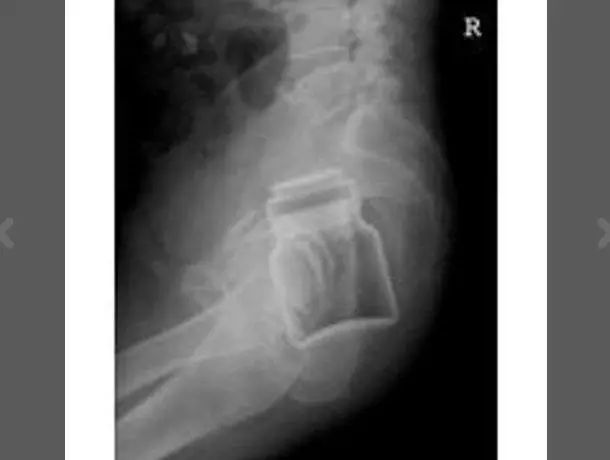

Pazze radiografie: gli oggetti che possono finire nel corpo umano

Oggetti bizzarri che hanno trovato la loro strada all'interno del corpo umano, e documentati grazie alle pazze radiografie raccolte dal dottor Frank Gaillard. Quest’ultimo ha fondato Radiopaedia.org, un sito collaborativo che raccoglie casi radiologici e articoli medici a tema.